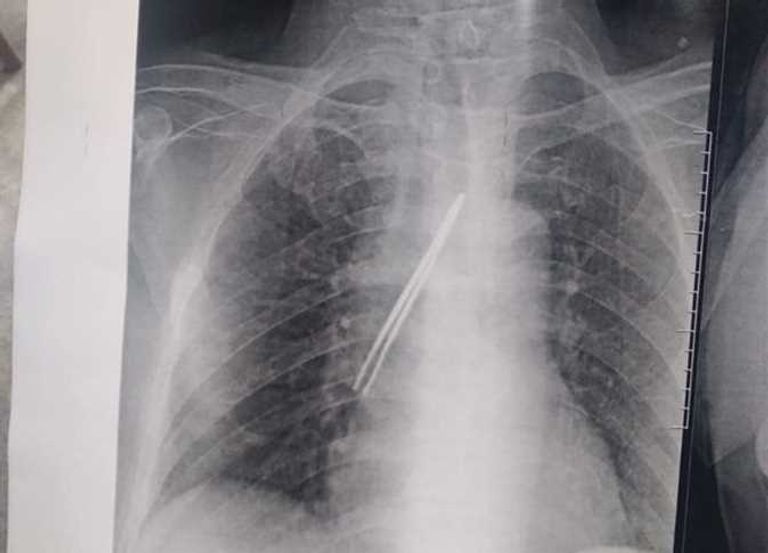

نجح فريق طبي في مستشفى بنها الجامعي بمحافظة القليوبية (دلتا مصر) في استخراج مِلقاط من القصبة الهوائية لمريض ابتلعه بالخطأ.

وأصدر مستشفى بنها بياناً كشف فيه تفاصيل الجراحة، وجاء فيه: "تمّ استخراج (مِلقاط شعر) من القصبة الهوائية لمريض يعاني من شق حنجري قديم".

وأضاف البيان: "المريض كان يقوم بتنظيف فتحة الشق الحنجري بطريقة غير صحيحة وغير طبية، عن طريق استخدامه ملقاط ملفوف بمناديل ورقية، وفوجئ بأن المِلقاط دخل إلى فتحة القصبة الهوائية".

وتابع: "حضر المريض إلى قسم جراحة القلب والصدر بمستشفى بنها الجامعي وهو في حالة اختناق، وتم دخوله إلى غرفة العمليات فوراً".

وختم البيان: "نجح الدكتور باسم مفرح الأستاذ المساعد بالقسم، وبمعاونة الدكتور أحمد الخضري مدرس مساعد التخدير، من استخراج (الملقاط)، وخرج المريض من العمليات، ويخضع الآن للمتابعة لاستكمال علاجه بالقسم لحين تماثله الكامل للشفاء".